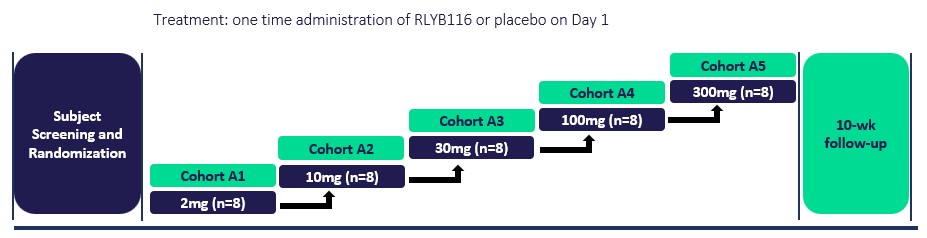

Our team has a track record of success in designing, developing, and securing marketing approval for C5 complement inhibitors, including Soliris and Ultomiris, for patients around the world with severe and rare complement-mediated diseases. Our most advanced product candidate in this therapeutic area is RLYB116, an inhibitor of C5, which is a central component of the terminal complement pathway. RLYB116 is an Affibody molecule attached to an albumin binding domain ("ABD") that has the potential to drive the rapid, complete, and sustained inhibition of C5 with a SC injection. We have completed a Phase 1 clinical trial in healthy participants that included the study of RLYB116 as both a single ascending dose (“SAD”) and a multiple ascending dose (“MAD”).

The SAD portion of the RLYB116 Phase 1 trial included five cohorts with doses ranging from 2mg up to 300mg. Data from the SAD portion of the RLYB116 trial showed that all study participants that were administered a single 1 mL SC injection of 100 mg of RLYB116 (n=6) demonstrated a reduction in free C5 greater than 99% within 24 hours of dosing. Subcutaneously administered RLYB116 in the SAD portion of the trial was observed to be generally well-tolerated at the 100 mg dose, with mild adverse events and no drug-related serious adverse events reported. The terminal elimination half-life of RLYB116 was greater than 300 hours. The MAD portion of the RLYB116 Phase 1 trial included an adaptive single-blind design with a four-week treatment duration to evaluate the safety, tolerability, PK, and PD of RLYB116 with multiple dose SC administration. The MAD portion of the trial included four cohorts: Cohort 1 (weekly dosing of 100 mg), Cohort 2 (3 doses of 100 mg the first week followed by weekly dosing), Cohort 3 (150 mg weekly dosing reduced to 125 mg weekly dosing) and

Cohort 4 (75 mg twice the first week followed by 100 mg twice per week) with post-treatment for 10 weeks. In December 2023, we reported data from the MAD portion of the trial that demonstrated a 100 mg low volume (1 mL) once-weekly dose of subcutaneously administered RLYB116 achieved sustained mean reductions in free C5 of greater than 93%, including at Day 29 with measurement prior to the last dose. The reduction from pre-treatment free C5 at 24 hours after the first dose of 100 mg was greater than 99%. In the MAD portion of the Phase 1 trial, RLYB116 demonstrated low inter-subject variability and consistent increases in exposure relative to dose with a mean estimated elimination half-life for RLYB116 of >300 hours. RLYB116 administered in the MAD trial as a 100 mg once-weekly dose was also observed to be generally well tolerated.

Based on the results of the RLYB116 Phase 1 trial, we conducted a series of biomarker characterization analyses. These analyses indicate the RLYB116 assay used to measure free C5 in the Phase 1 trial overestimated the levels of free C5 by approximately ten-fold, indicating that RLYB116 produced greater complement inhibition than initially reported. We now believe that RLYB116 has the potential to be an effective treatment for patients with a variety of complement-mediated diseases, including PNH, gMG and antiphospholipid syndrome ("APS"). We also completed manufacturing process enhancements with a goal of further improving the tolerability of RLYB116. Based on the results of enhanced analytical techniques, including mass spectrometry, these process enhancements have successfully further purified the RLYB116 drug substance. As a result, we believe that RLYB116 will have a favorable tolerability profile at doses at and above those evaluated in the Phase 1 MAD trial. We plan to initiate a RLYB116 confirmatory clinical PK/PD trial in the second quarter of 2025 to demonstrate improved tolerability as well as complete and sustained complement inhibition. This single-blind MAD trial will evaluate a 4-week treatment duration that will include two cohorts of eight participants each. Our current plan is that Cohort 1 will evaluate weekly dosing of 150 mg and Cohort 2 will evaluate weekly dosing of 225 mg with 10 weeks of follow-up after the conclusion of treatment.